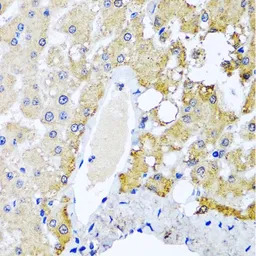

IHC-P analysis of human liver damage tissue using GTX55811 SULT1A1 antibody.

Dilution : 1:100